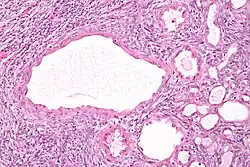

Micrograph of a cystic nephroma. H&E stain.